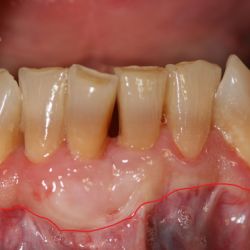

Caso de cirugía periodontal

Cirugía periodontal en un paciente